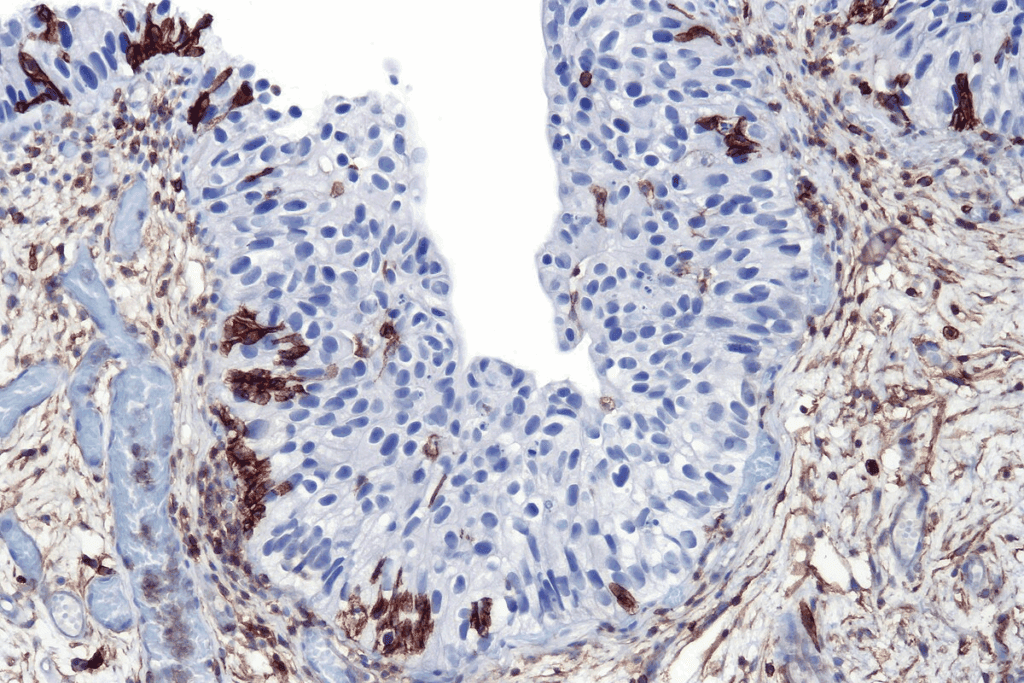

CIS is different from invasive cancer because CIS cells haven’t crossed the basement membrane. This thin layer of tissue keeps cells in place. Invasive cancer, on the other hand, has spread past this membrane.

CIS cells are different from normal cells. They haven’t invaded the basement membrane yet. This is a key difference that sets CIS apart from invasive cancer.

| CIS Cells | Disorganized | Present | No Stromal Invasion |

CIS cells look abnormal under a microscope. They have unique features that show they’re not normal cells. But, they don’t invade the surrounding stroma.